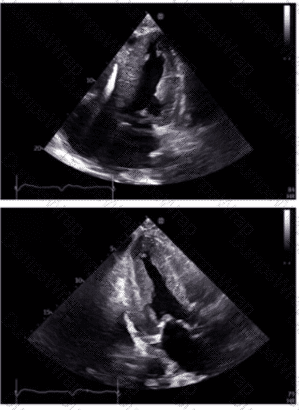

Which diagnosis is most consistent with the findings in these images?

The first image shows a bullseye plot of global longitudinal strain (GLS) with marked reduction in strain values (less negative numbers) most prominently in the apical segments (central red zone), with an overall GLS of -8.2% (normal is about -20%) and a reduced ejection fraction of 41%. This pattern is characteristic of Takotsubo cardiomyopathy, which typically demonstrates regional wall motion abnormalities that predominantly involve the apex and mid segments of the left ventricle with basal sparing.

The 2D echocardiographic images show apical ballooning, a hallmark of Takotsubo cardiomyopathy, where the apex is akinetic or dyskinetic and the basal segments contract normally or hypercontract. Doppler images show findings consistent with impaired ventricular function.

In contrast:

Apical hypertrophic cardiomyopathy (HCM) would show increased wall thickness localized to the apex but not apical ballooning or reduced strain in that typical pattern.

Hypertrophic obstructive cardiomyopathy (HOCM) involves basal septal hypertrophy with outflow obstruction, not apical akinesis or ballooning.

Restrictive cardiomyopathy from amyloidosis involves diffuse infiltration and generally a different strain pattern with more uniform reduction and “apical sparing” rather than apical involvement.

This interpretation aligns with the diagnostic criteria and echocardiographic features described in the adult echocardiography literature, including the "Textbook of Clinical Echocardiography" (Chapter on Cardiomyopathies) and ASE guidelines, which highlight apical ballooning and regional strain abnormalities as diagnostic features of Takotsubo cardiomyopathy【16:Cardiomyopathy Chapter†Textbook of Clinical Echocardiography, 6e】【12:ASE Guidelines on Strain Imaging†p.130-135】.